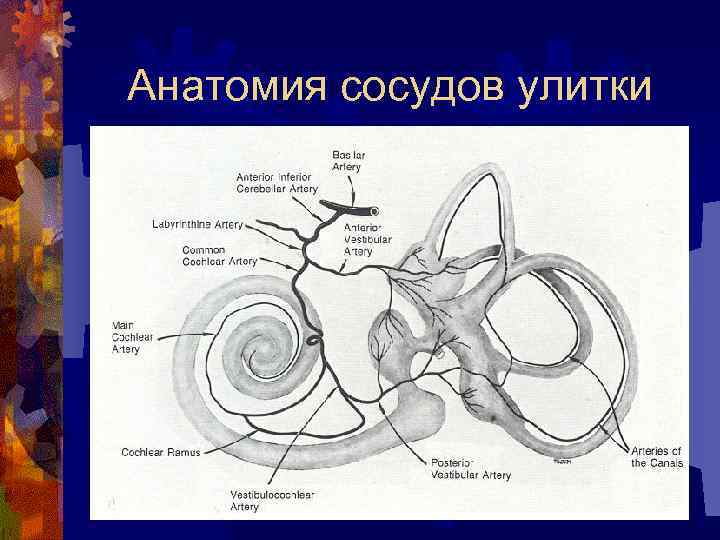

Анатомия сосудов улитки